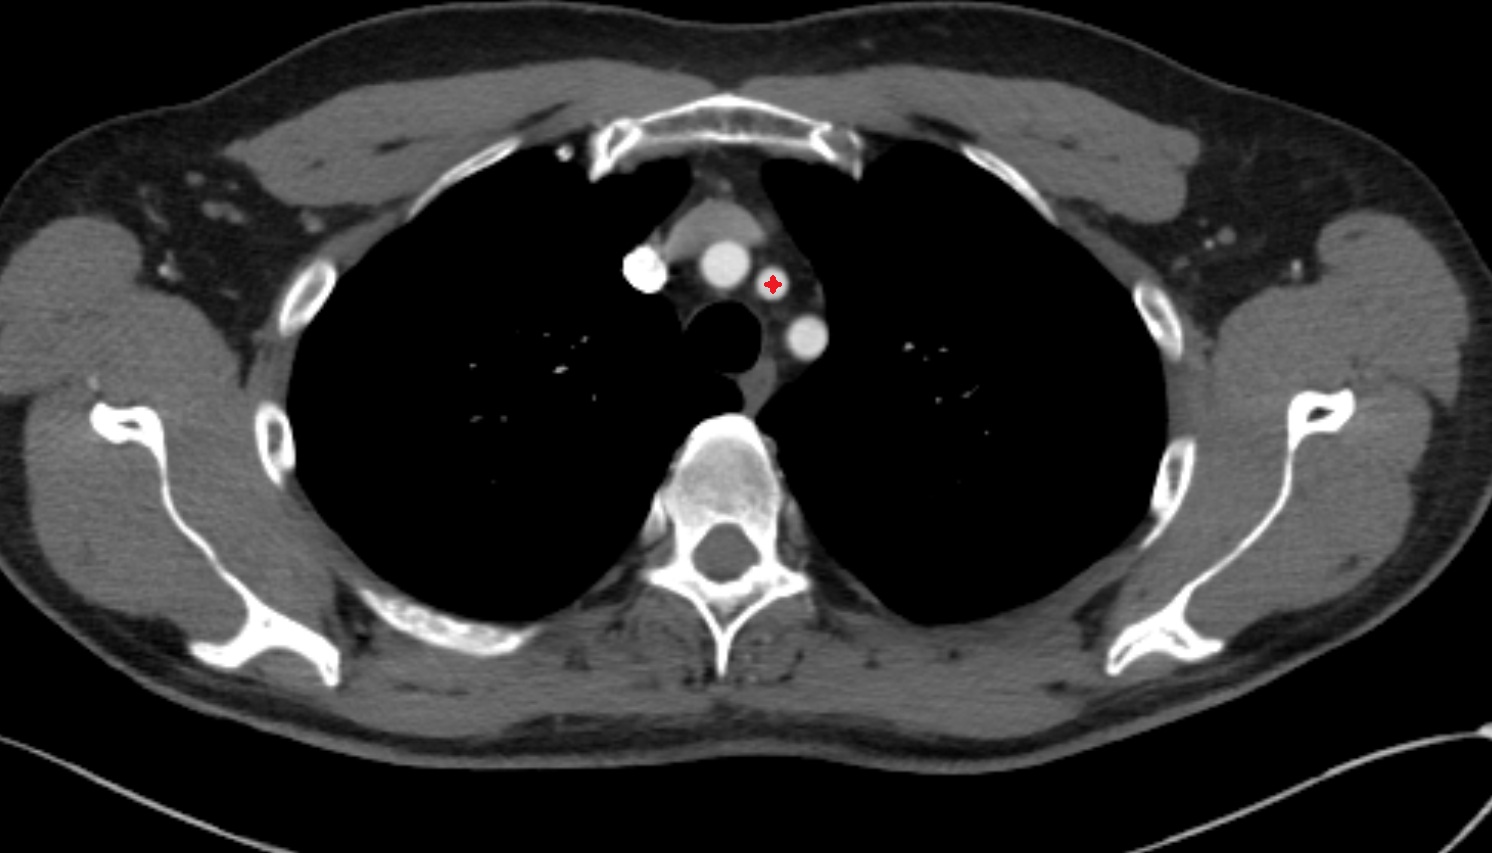

- Brachiocephalic trunk

- Common carotid artery

- Subclavian artery

- Right subclavian artery